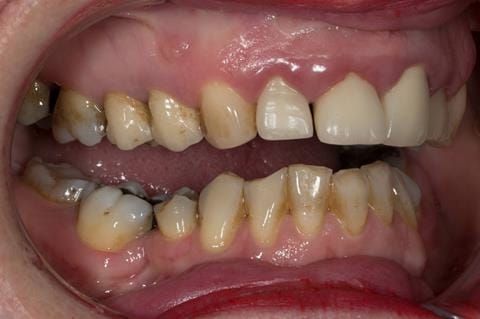

Provision of a maxillary cobalt chromium based partial denture/protective occlusal splint in a heavily restored dentition

- UR2 peri-radicular periodontitis with a peri-radicular area on the root apex. Retrograde amalgam filling from a previous apicectomy. No visible root canal or root canal filling. Large circumferential marginal gap between the crown and tooth. Large post and core present. Very little tooth structure remaining resulting in a fragile tooth with increased potential for fracture.

- UR1 peri-radicular periodontitis with a small peri-radicular area on the root apex with wide blunderbuss apex. Radio-opaque root canal filling present approximately 3 mm short of the radiographic apex. Large circumferential marginal gap between the crown and tooth. Large post and core present. Very little tooth structure remaining resulting in a fragile tooth with increased potential for fracture.

- UL1 peri-radicular periodontitis with a peri-radicular area on the root apex. Retrograde amalgam filling from a previous apicectomy. Visible root canal space with no sign of root canal filling. Large circumferential marginal gap between the crown and tooth. Large post and core present. Very little tooth structure remaining resulting in a fragile tooth with increased potential for fracture.

- UL2 peri-radicular periodontitis with a peri-radicular area on the root apex. No visible root canal or root canal filling. Large circumferential marginal gap between the crown and tooth. Large post and core present. Very little tooth structure remaining resulting in a fragile tooth with increased potential for fracture.

- High smile line showing gum above gingival zeniths of upper front teeth when smiling. Aesthetic failure of the upper four incisors with inflammation of the gingivae and mis-match of the gingival zenith levels.

- Other than the maxillary incisors the remaining dentition was in marginally better condition being moderately to heavily restored. Many will probably require replacement and restoration from time to time mainly from wear and tear owing to occlusal forces.

Following consultation and second discussion appointment the patient chose to have option 3 namely, a maxillary cobalt chromium based partial denture/protective occlusal splint. The clinical situation and treatment process is shown in detail below with photographs. The patient was successfully rehabilitated with this and her quality of life considerably improved. The clinical work was provided by Finlay and the technical work by Rowan.